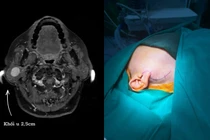

Tại bệnh viện, bệnh nhân được chỉ định nội soi tiêu hóa bằng công nghệ NBI. Qua thăm khám, các bác sĩ ghi nhận niêm mạc đại tràng xuống và đại tràng góc lách xung huyết. Đáng chú ý, tại trực tràng phát hiện một khối u kích thước khoảng 1,2cm, màu vàng nhạt.

Hình ảnh khối u kích thước khoảng 1,2cm, màu vàng nhạt trên nội soi - Ảnh BVCC

Các bác sĩ đã thực hiện nội soi cắt bỏ hoàn toàn khối u bằng kỹ thuật cắt tách dưới niêm mạc (ESD). Phương pháp này giúp loại bỏ triệt để tổn thương, bảo tồn toàn vẹn trực tràng cho người bệnh, đồng thời giúp bệnh nhân tránh phải phẫu thuật xâm lấn.

Mẫu bệnh phẩm sau khi cắt được gửi làm giải phẫu bệnh và xác định là u Carcinoid trực tràng, các diện cắt không còn tế bào u.